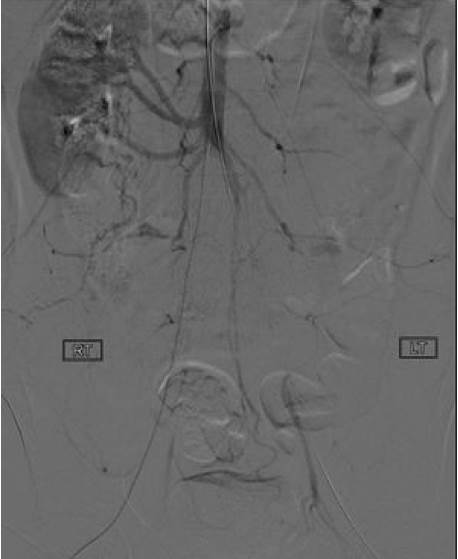

“Por el CT Scan que se le realizó se reflejó una oclusión de aorta infrarrenal con envolvimiento de ambas arterias ilíacas comunes, y aún los síntomas que presentó eran leves. También se le halló trombosis profunda de la vena poplítea (vena femoral que desemboca en en la vena ilíaca externa) en ambas extremidades con un trombo flotante en la vena cava inferior (Vena grande que desemboca en el corazón). Al paciente se le aplicó terapia trombolítica para romper los coágulos y cuando se le fue a hacer el arteriograma de seguimiento no hubo mejoría y se decidió realizar una cirugía abierta”, explicó primeramente el Dr. Fraticceli.